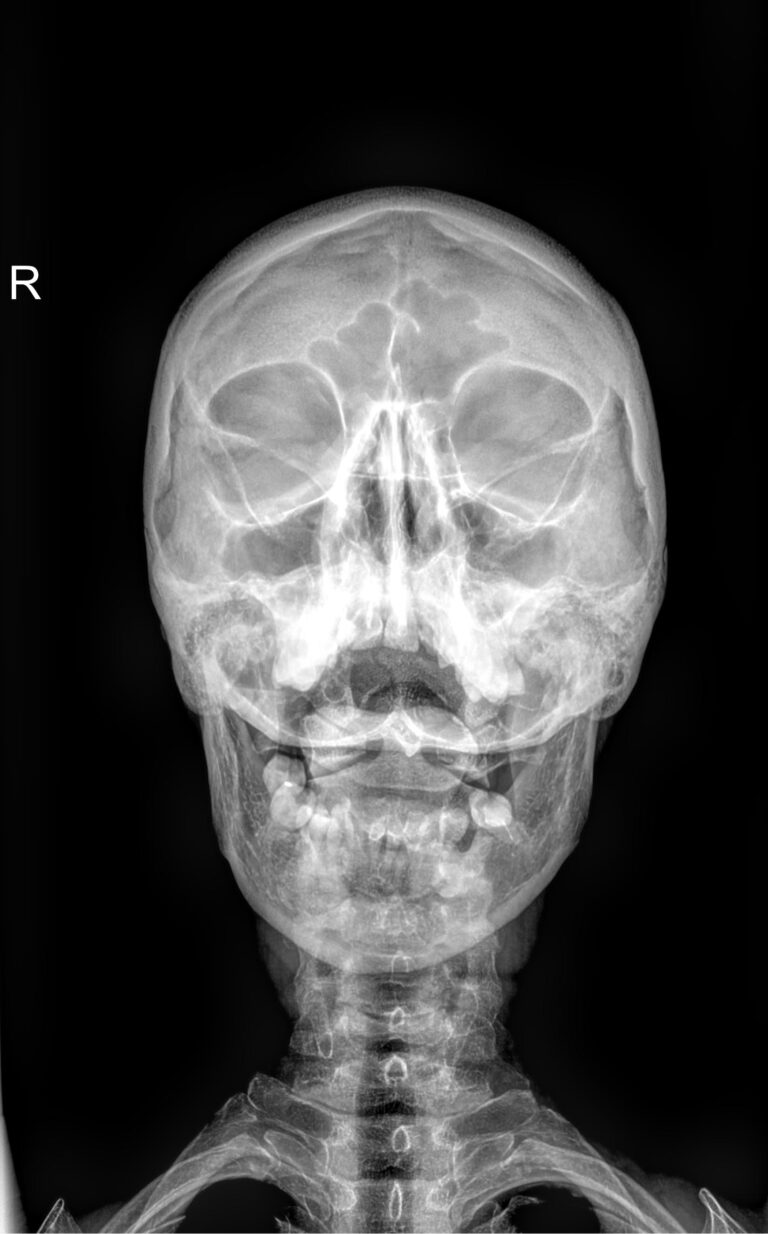

• Прямой ― лежа прямо на спине. Дает возможность увидеть средние и нижние, а также первые грудные позвонки:

• «Через открытый рот» ― то же положение, только необходимо как можно ниже опустить нижнюю челюсть, не запрокидывая сильно голову. Аппарат при этом не касается тела. В этом положении отчетливо видны 2 верхних позвонка и их сочленение, нижняя челюсть их не закрывает;

• Боковой ― сидя или стоя боком к пластине детектора. У большинства людей видны все 7 позвонков, у пациентов с короткой шеей нижние могут быть закрыты плечами;

• Стоя так же боком, запрокинуть голову назад;

• В том же положении согнуть голову на грудь. Оба теста позволяют отследить патологическую подвижность или функциональный блок, которые не видны в предыдущих, нейтральных позициях, на всем протяжении шеи.